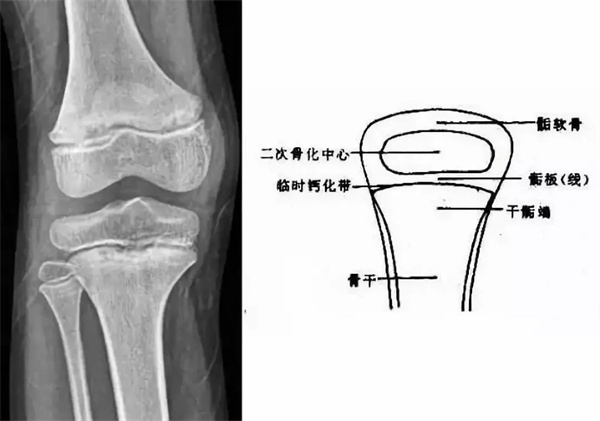

我們都知道,人體的高矮是由骨骼的生長發(fā)育決定的,特別是下肢長骨。長骨呈長管狀,在長骨的兩端有一種專管骨骼生長的骺軟骨,它與干骺端之間有一盤狀軟骨結構稱為骺板(線),在幼兒的X光片上表現(xiàn)為一條較寬的透光帶。(見下圖)

未成年時隨著年齡的增加骺軟骨端不斷骨化,骨骼就不斷增長。當骨骺線完全閉合時骨骼就停止生長,個子也就不再增長了。一般骨骺端完全閉合的年齡是18~20歲左右。